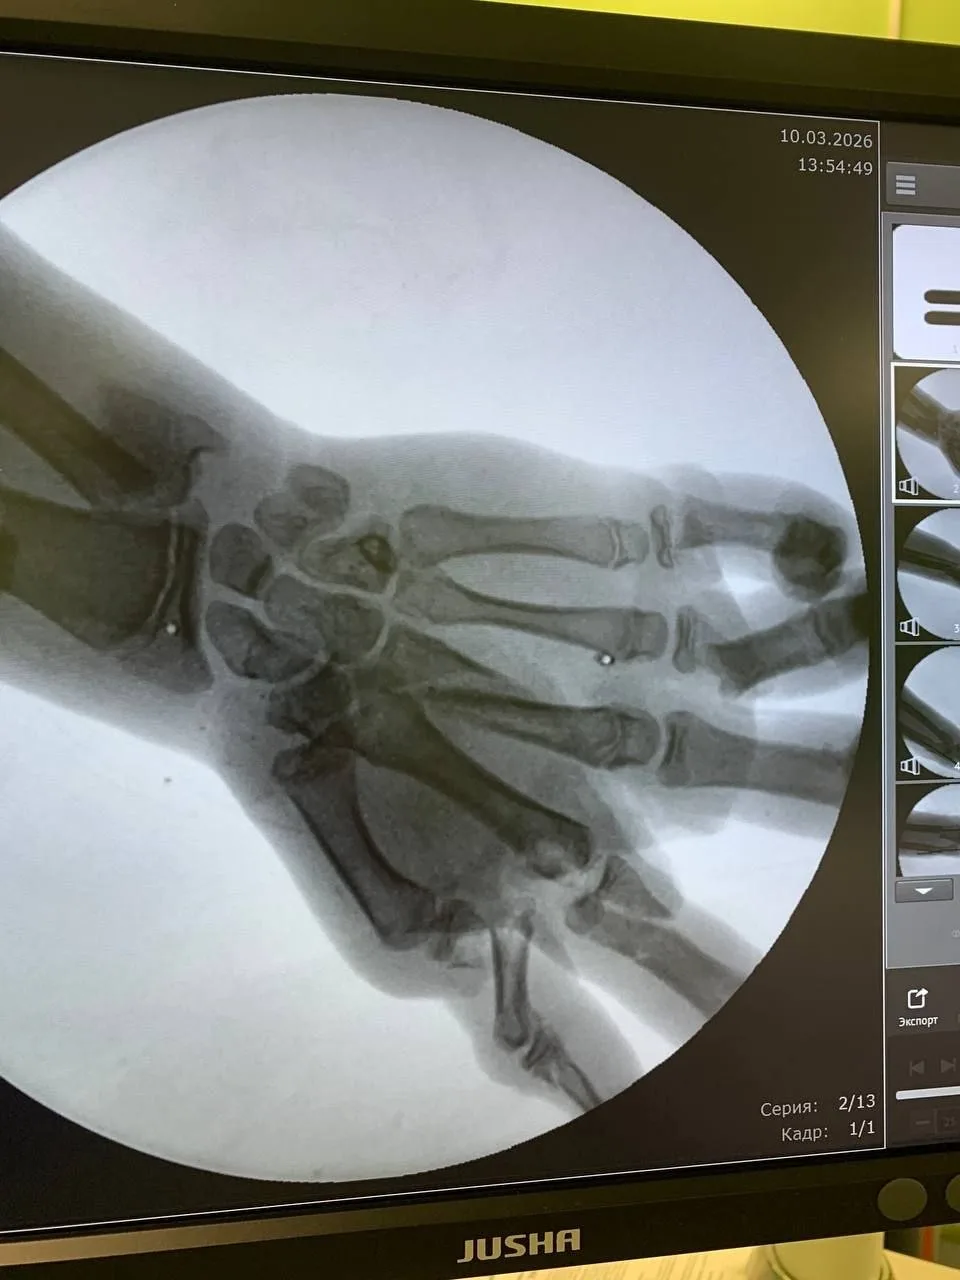

- 11:37 В Калининграде врачи Детской областной больницы спасли кисть подростка после взрыва снаряда

- В Калининграде врачи Детской областной больницы спасли кисть подростка после взрыва снаряда